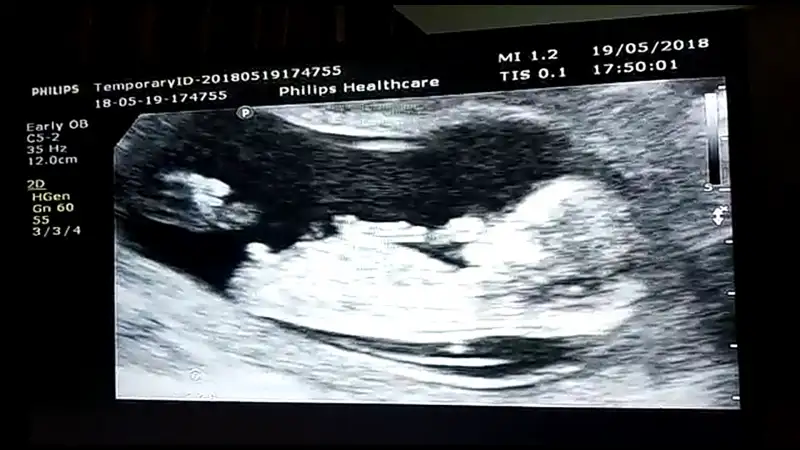

Bunu görmemek için kör olmak lazımEki Görüntüle 2149591

Kızlar ben son gittiğim muayeneden foto atmayı unutmuşum :) burada 12+6 haftalık. Bakın bakalım doktorun gördüğü pipişkoyu siz de görecek misiniz

Bunu görmemek için kör olmak lazımBize böyle resimler attın da yanıldık mı?